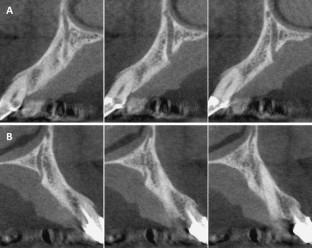

Fig. 2